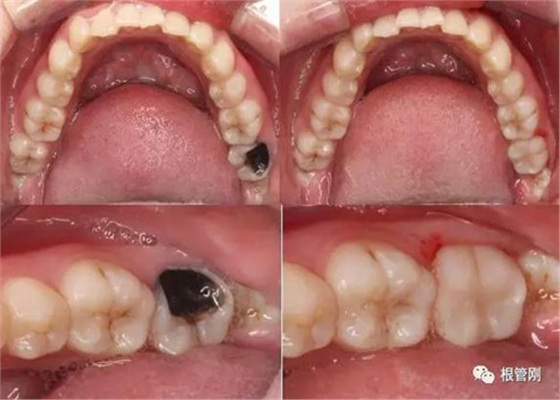

這是一顆嚴(yán)重的蛀牙,顏色發(fā)黑,牙齒的一半已經(jīng)崩解,看到此情此景,也許很多人會(huì)想它的神經(jīng)肯定死掉了吧?它還有救嗎?應(yīng)該會(huì)做根管治療+牙冠修復(fù)吧?

經(jīng)細(xì)致的詢問(wèn)病史(有沒(méi)有自發(fā)痛,冷熱刺激敏感等)、仔細(xì)的檢查(包括探診,冷診,熱診,叩診以及牙片的檢查不可缺少),綜合各種信息判斷,得出準(zhǔn)確的診斷為深齲,在與患者溝通,患者同意直接樹(shù)脂修復(fù)!